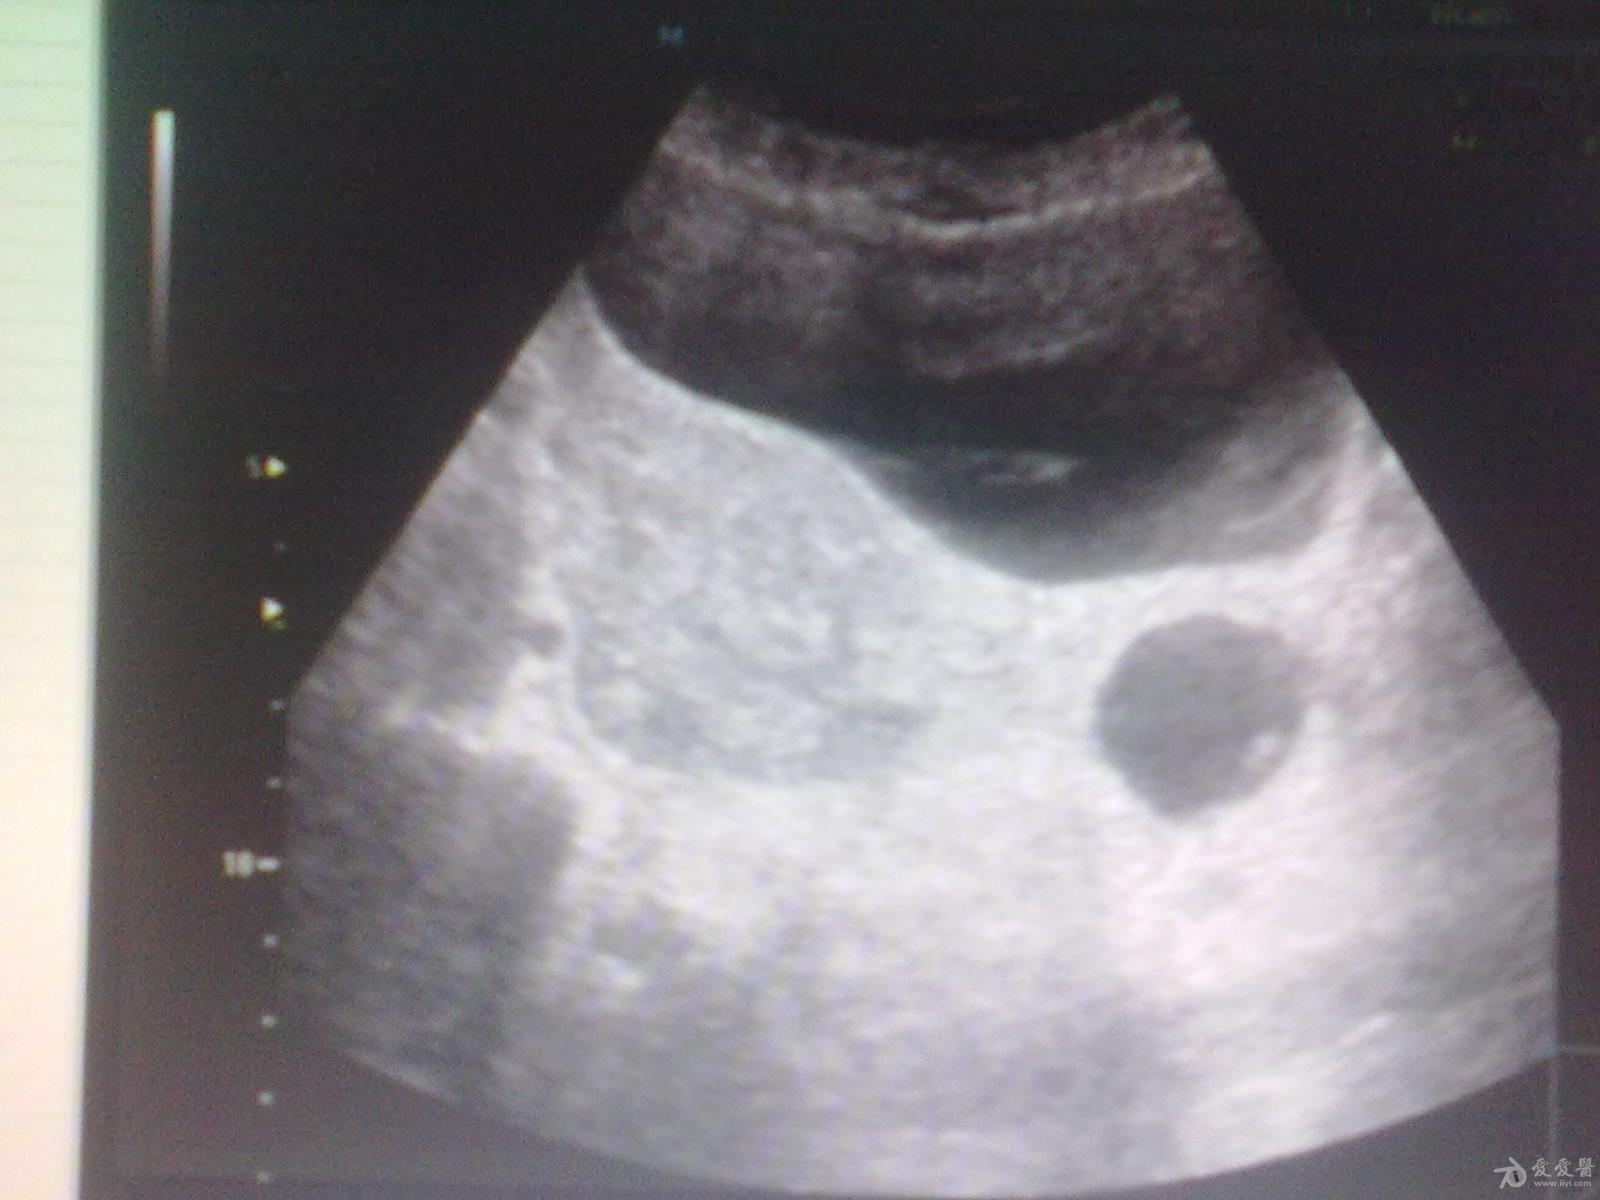

左侧卵巢囊肿?

39岁女性继发性

不孕

,月经第12天

超声

检查:左侧附件区见大小约3.6x2.7cm类圆形无回声,边界清,内透声好,右侧卵巢建多个大小不等极不规则囊泡回声,最大约1.2x1.4cm。这几幅图探头标记都在患者的右侧,也就是标记冲向我。,,显示器上的M标记在显示器的左上方。囊肿是在左侧卵巢吗?